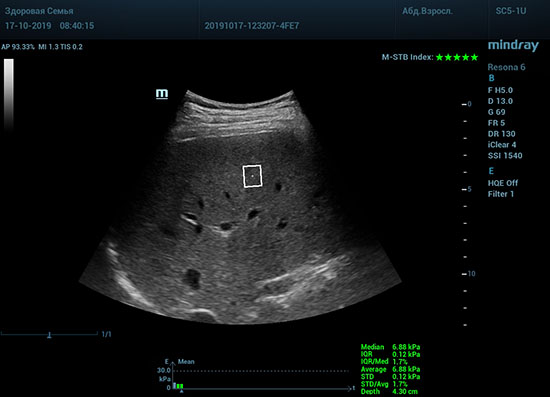

Определение плотности печени. Не ошибся ли оператор при измерении эластических свойств печени? Для оценки критериев качества предусмотрен индекс MBT, который покажет насколько «твердой» была рука оператора и двигалась ли печень. При MBT 5* рука тверда и показатели достоверны. Для оценки качества результатов используется IQR индекс, отображающий колебания показателей в точке измерения при расчете медианы. Показатели при IQR <30% считаются приемлемыми. Техника сканирования через межреберные промежутки требует размещение окна интереса на несколько сантиметром ниже капсулы, для исключения эффекта реверберации. Установка ROI на паренхиму без захвата сосудов, для исключения погрешностей измерения.

Стадия фиброза определяется по системе METAVIR Staging, построенной на данных биопсии и сопоставлении с данными эластографии. Своевременная диагностика фиброза, и начало его лечения, залог благоприятного исхода заболевания.